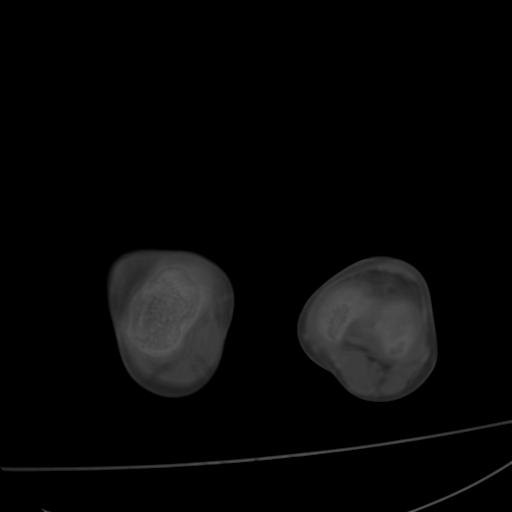

标题: PED0940:M12Y,左股骨下端酸痛畸形 [打印本页]

标题: PED0940:M12Y,左股骨下端酸痛畸形

12岁男孩,左膝关节肿痛8年,近月明显

内生骨软骨瘤?

血友性关节病?